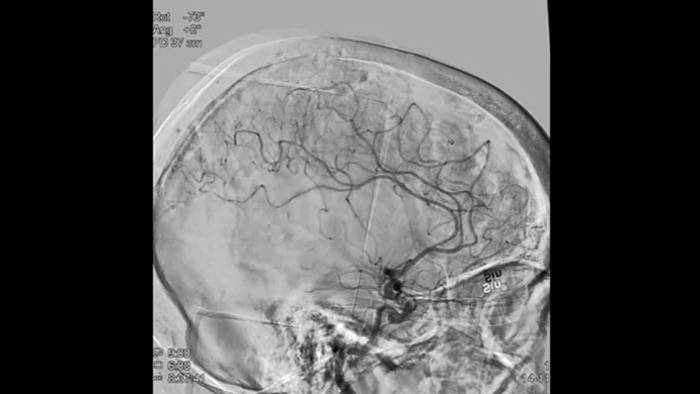

Mejore la visualización de la vasculatura

Roadmap Pro

Tome decisiones informadas sobre si se puede alcanzar el coágulo y qué vía utilizar. Roadmap Pro, un avanzado mapa de doble contraste, ayuda a mejorar la visualización de los vasos superpuestos, a la vez que equilibra la exposición a la radiación.